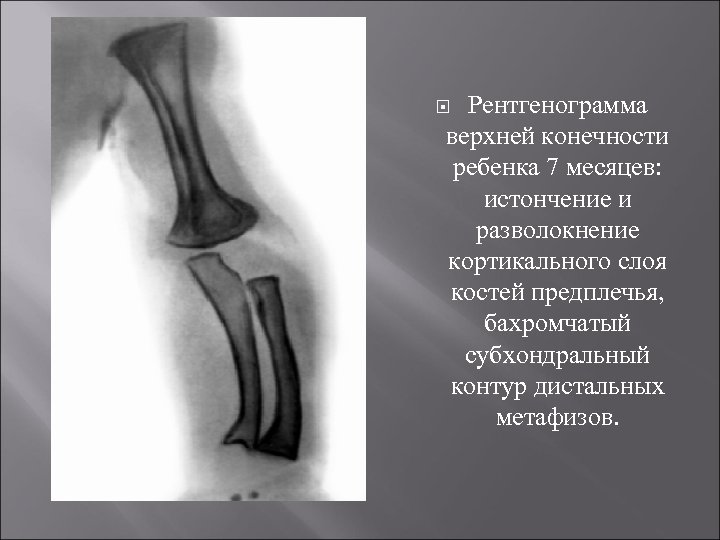

Рентгенограмма верхней конечности ребенка 7 месяцев: истончение и разволокнение кортикального слоя костей предплечья, бахромчатый субхондральный контур дистальных метафизов.

Диагноз основывается на данных анамнеза клинической симптоматике, результатах биохимических исследований (содержание фосфора и кальция в крови и моче, активность щелочной фосфатазы и др. ), рентгенологических исследования скелета. Рентгенологические изменения в скелете появляются позже клинических симптомов и не ранее 6 -месячного возраста. Степень выраженности их зависит от тяжести процесса. На фоне распространенного остеопороза, малоконтрастного, нечеткого рисунка костей между эпифизами и метафизами (зоны предварительного обызвествления) определяются широкие полосы разрежения, отграниченные рыхлыми бахромчатыми контурами смежных поверхностей эпифиза и метафиза В области диафизов длинных трубчатых костей корковый слой истончен, выглядит слоистым, контуры его как со стороны костномозгового канала, так и снаружи становятся нечеткими, смазанными Длинные трубчатые кости, особенно нижних конечностей, дугообразно деформированы. Рахитическая соха vara характеризуется деформацией вертельной области бедра. Большеберцовые кости изогнуты кнаружи с вершиной деформации на границе средней и дистальной частей, при этом кортикальный слой утолщен по медиальной и задней поверхностям кости. Нередко в области диафизов длинных трубчатых костей видны Лоозера зоны, возможны поднадкостничные переломы. Рентгенологическое исследование других отделов скелета (позвоночника, черепа, ребер) нецелесообразно, т. к. клинически выявляемые изменения в них достаточно характерны. Повторные рентгенограммы длинных трубчатых костей производят с целью контроля за эффективностью лечения. При благоприятном течении процесса структура и контуры костей становятся более четкими, вблизи эпифизарных ростковых зон появляются поперечные зоны обызвествления, которые, постепенно расширяясь, сливаются с метафизами. Чередование плотных и более светлых полос свидетельствует о волнообразном течении процесса